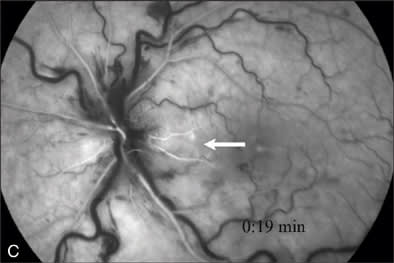

At our initial examination in August 2008, corrected visual acuity was 20/30 in the right eye and 20/50 in the left, with normal ocular pressure in both eyes. There were no rubeosis irides in either eye. Fundus examination appeared normal in the right eye while the left eye revealed a typical nonischemic CRVO (Figure 1A). Fluorescein angiography of the left eye (Figure 1B to 1E) showed generalized dilated, tortuous retinal veins, intraretinal hemorrhages, peripheral retinal non-perfusion areas, and microvascular leakage at the macula (Figure 1E, arrow). Despite the peripheral retinal ischemia, the macula itself was not ischemic at the first visit, as evidenced by the early phase FA showing 2 cilioretinal arteries supplying the fovea (Figure 1C, arrow). Spectral domain OCT (OPKO-OTI, Miami, FL.) confirmed the diagnosis of cystoid macular edema (CME). The patient got intravitreal bevacizumab (Avastin) injection (1.25 mg/0.05 mL) at the first visit.

Figure 1 A–G |